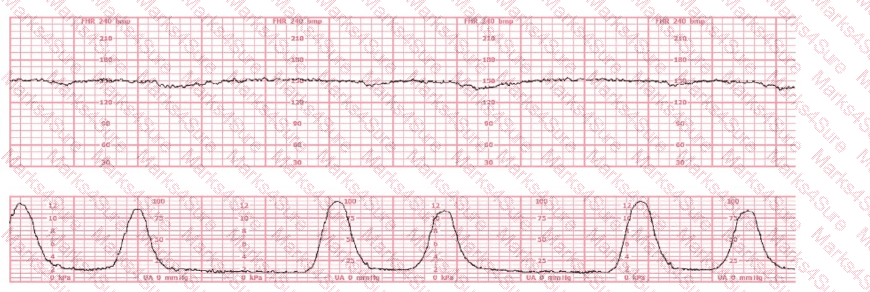

A woman is being induced with oxytocin. The tracing shown is representative of 20 minutes. Based on this tracing, the next step would be to: